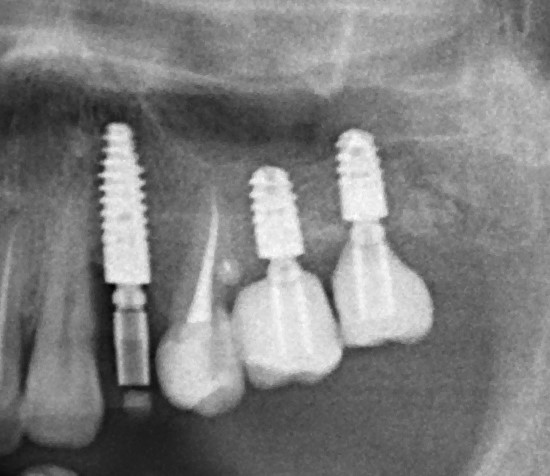

Для этого мы сделали КЛКТ:

И КЛКТ показала нам, что с имплантатами и окружающей костью всё зашибись. Через 12 лет после операции, отсутствия наблюдения, пофигизма в замене временных коронок! Нужны ли тебе еще какие-нибудь доводы в пользу долгосрочной эффективности метода?

Серия контрольных снимков на этапах:

Вот так закончилась 12-летняя эпопея Зинаиды с восстановлением зубов на нижней челюсти. Через пару дней она уехала на экскурсию в Санкт-Петербург (на всякий случай, мы попросили задержаться в России, вдруг потребуется коррекция), а оттуда — домой, в дружественную страну. Судя по тому, что она нам пишет — у неё всё прекрасно и хорошо. Зинаида обещает не пропускать профилактические осмотры и наблюдаться у стоматолога по месту жительства.